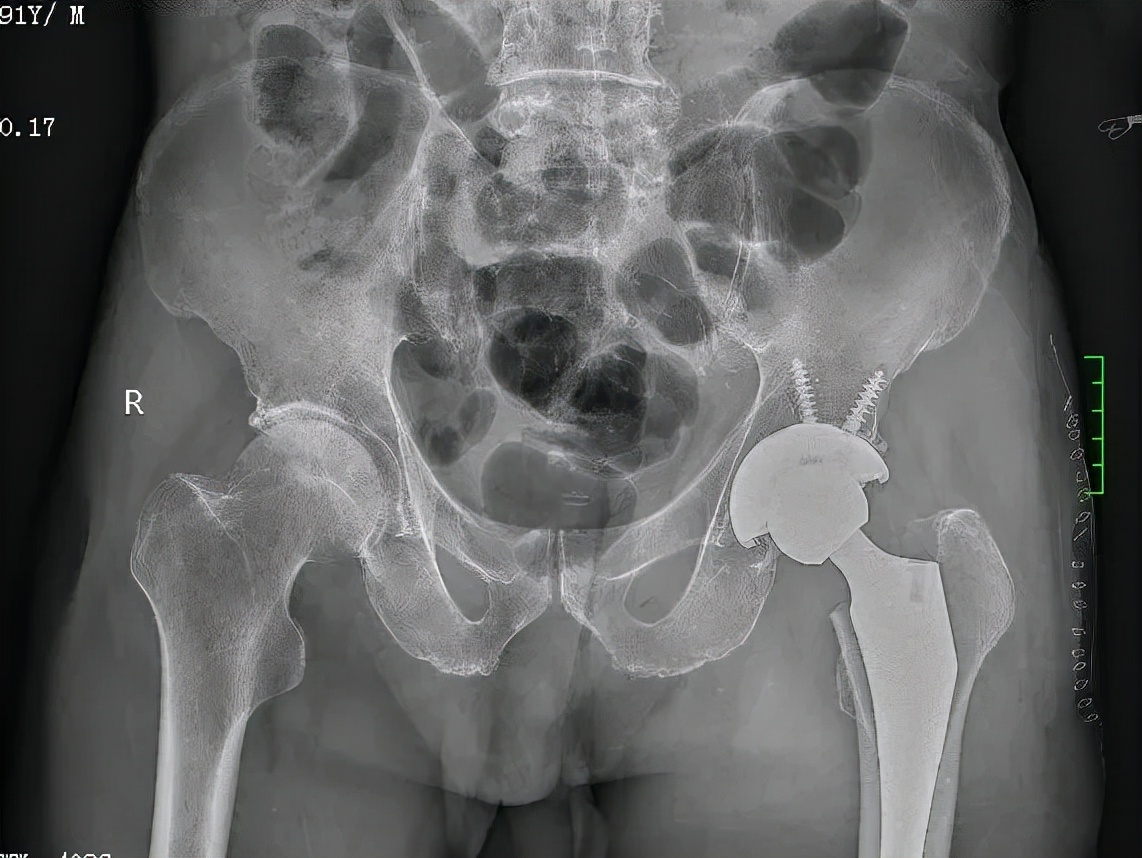

术后图

黄爷爷因摔伤致左侧股骨颈骨折到关节外科住院治疗。考虑到他已经91岁高龄,家人一开始倾向于选择保守治疗而非手术治疗。入院后,专家为他进行综合评估,征得家属及本人同意后,选择国内外快优康复的治疗标准,为他实施人工全髋关节置换术。在麻醉专家李喜松、黄红梅进行神经阻滞后,关节外科陆吉利、农家隆、陈俊、胡国芳四位专家共同为他进行手术。手术效果明显,术后第二天,患者在家人的协助下,可以使用助行器下床活动。术后第三、第四天,患者已能自行使用助行器下床活动。家属很激动地对医护人员说:“要是不做手术,老人家很痛苦,每天卧床不起,给家里人带来极大的护理负担。手术后,老人能自行活动,极大改善了生活质量。”

91岁股骨颈骨折患者要做全髋置换还是半髋置换?关节外科主治医师胡国芳表示,半髋置换也叫股骨头置换,是换去股骨头而没有进行髋臼置换的手术。这种手术一般适用于七十岁以上、活动量少、体质较弱的老年人,此类病人,需要尽量选择手术时间短,操作相对简单的术式来解决问题。全髋关节置换就是股骨头和髋臼都进行置换,这种手术常用于七十岁以下、活动量大、骨质好、身体好的病人。

对于选择半髋置换还是全髋置换,年龄不是唯一衡量标准,还需要结合患者摔伤之前的生活状态:身体健康情况、平时的运动量等,如果平时运动量较大,每天散步2-3公里以上,术后预计运动量同前,可选择全髋关节置换,这也是黄爷爷选择人工全髋关节置换治疗的原因。如果患者术前运动量不大,术前仅能生活自理,患者术后的运动量也不大,半髋置换已经足够使用。当然在患者身体情况及手术时间允许情况下,尽量选择全髋关节置换术,因为目前人民生活水平提高,再加上目前医疗技术水平的进步,平均寿命延长了,选择全髋置换可以提高髋部的耐磨度,避免髋臼磨穿等并发症出现。